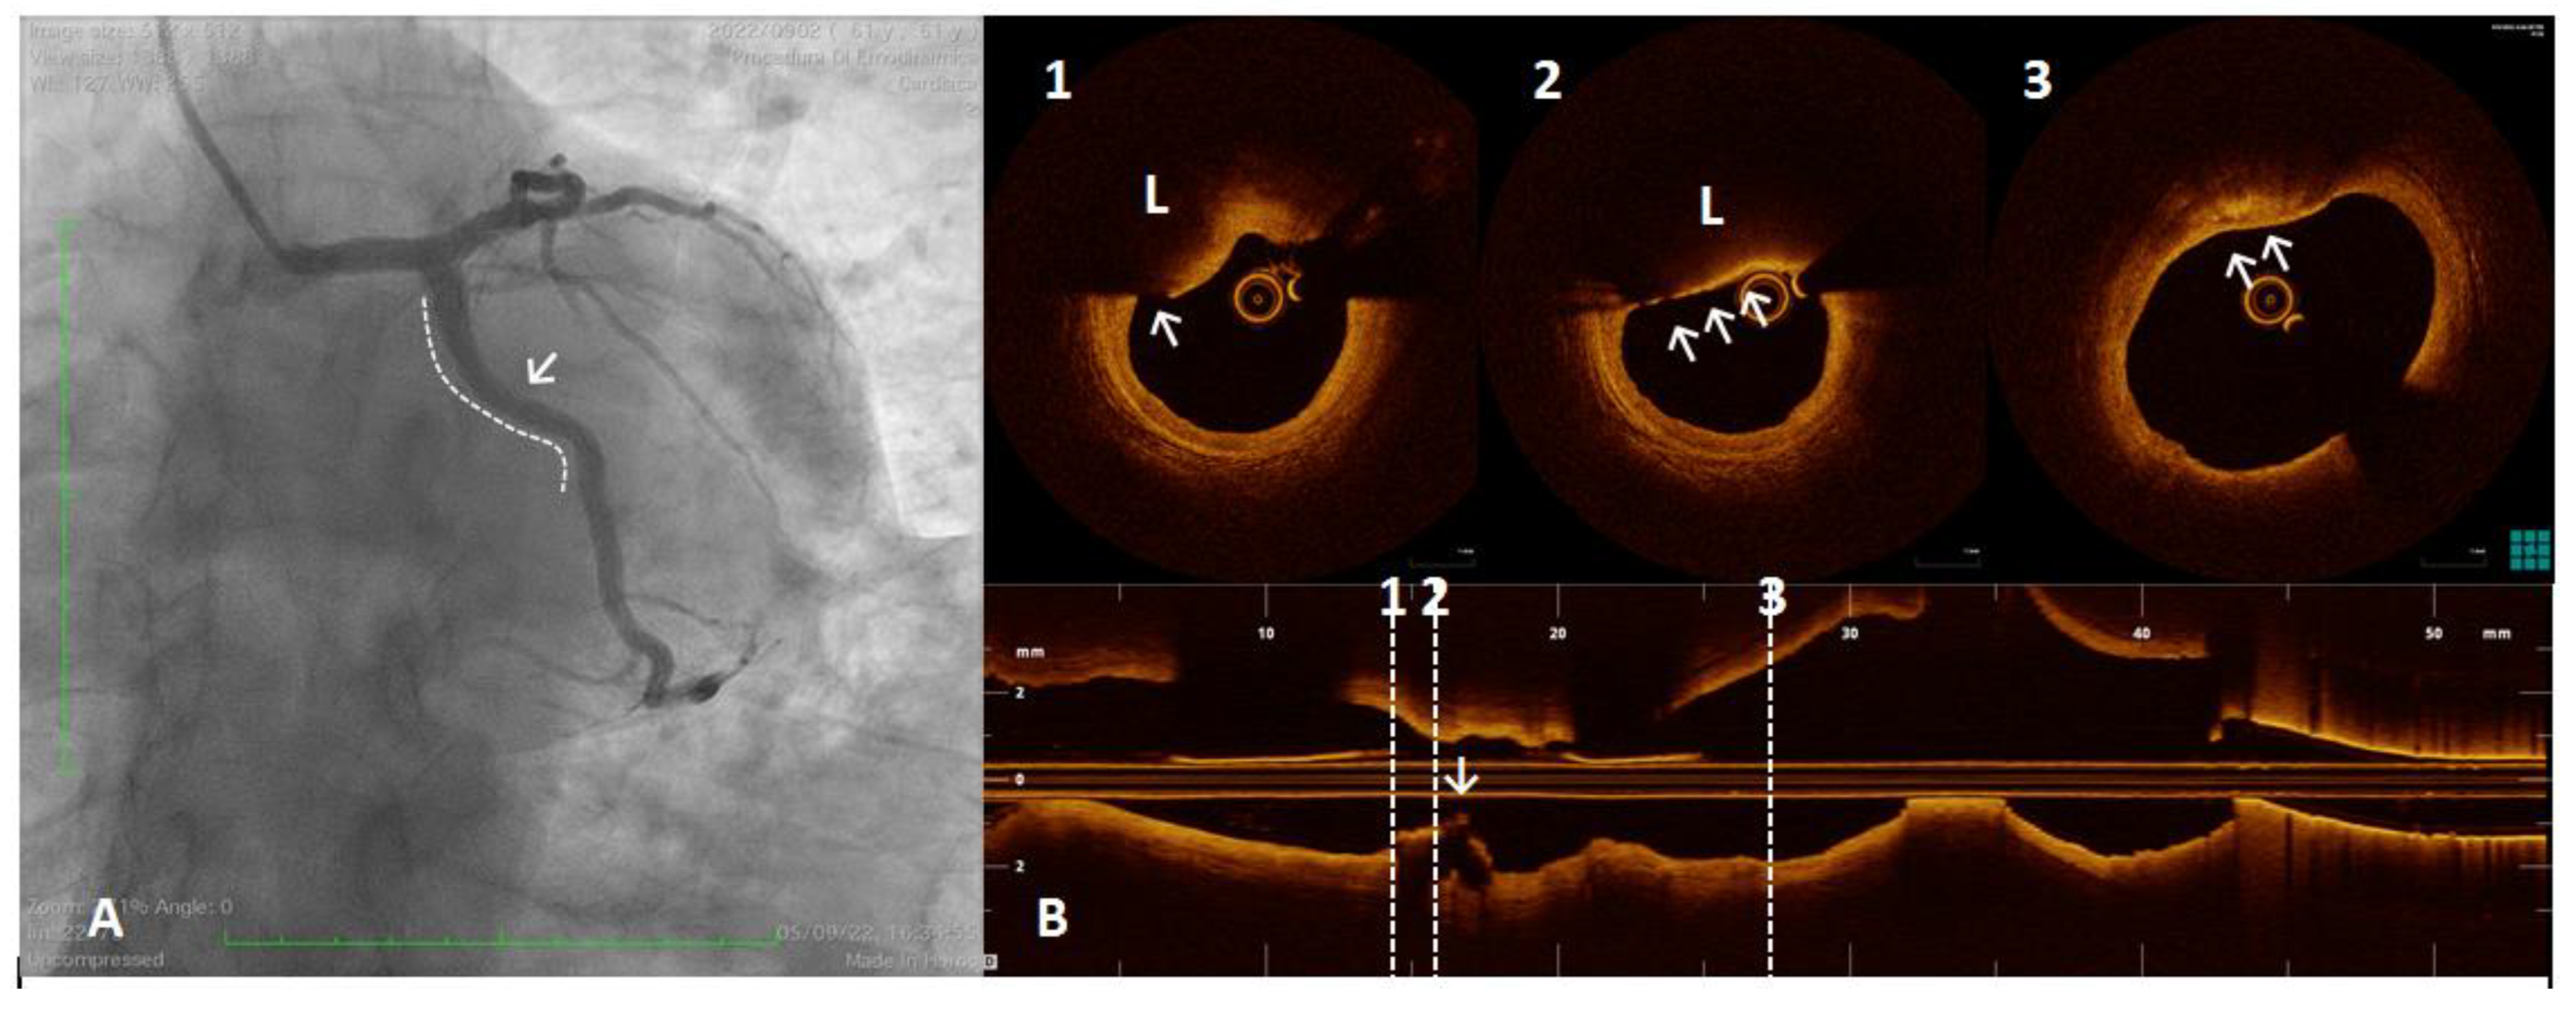

- Partida, R.A.; Libby, P.; Crea, F.; Jang, I.-K. Plaque erosion: A new in vivo diagnosis and a potential major shift in the management of patients with acute coronary syndromes. Eur. Heart J. 2018, 39, 2070–2076. [Google Scholar] [CrossRef]